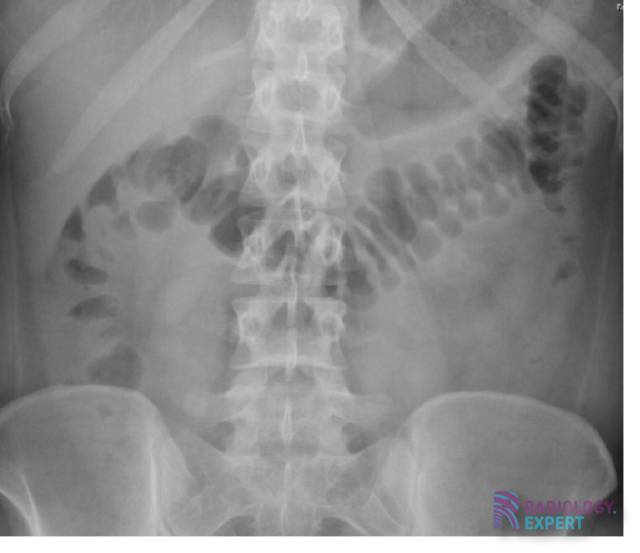

X-Buikoverzicht

De basis principes van het X-buikoverzicht onderzoek.

Ondanks dat het X-buikoverzicht tegenwoordig minder vaak uitgevoerd wordt, heeft het nog steeds in bepaalde situaties een klinische waarde. Enige kennis over dit onderzoek is dan ook essentieel. Belangrijke onderwerpen zijn o.a. volvulus, vrij lucht en nefrolithiasis.

• Ileus

• Sigmoïd volvulus

• Caecum volvulus

• Vrij lucht

• Nefrolithiasis

• Urolithiasis

• Nefrocalcinose

• Corpus liberum